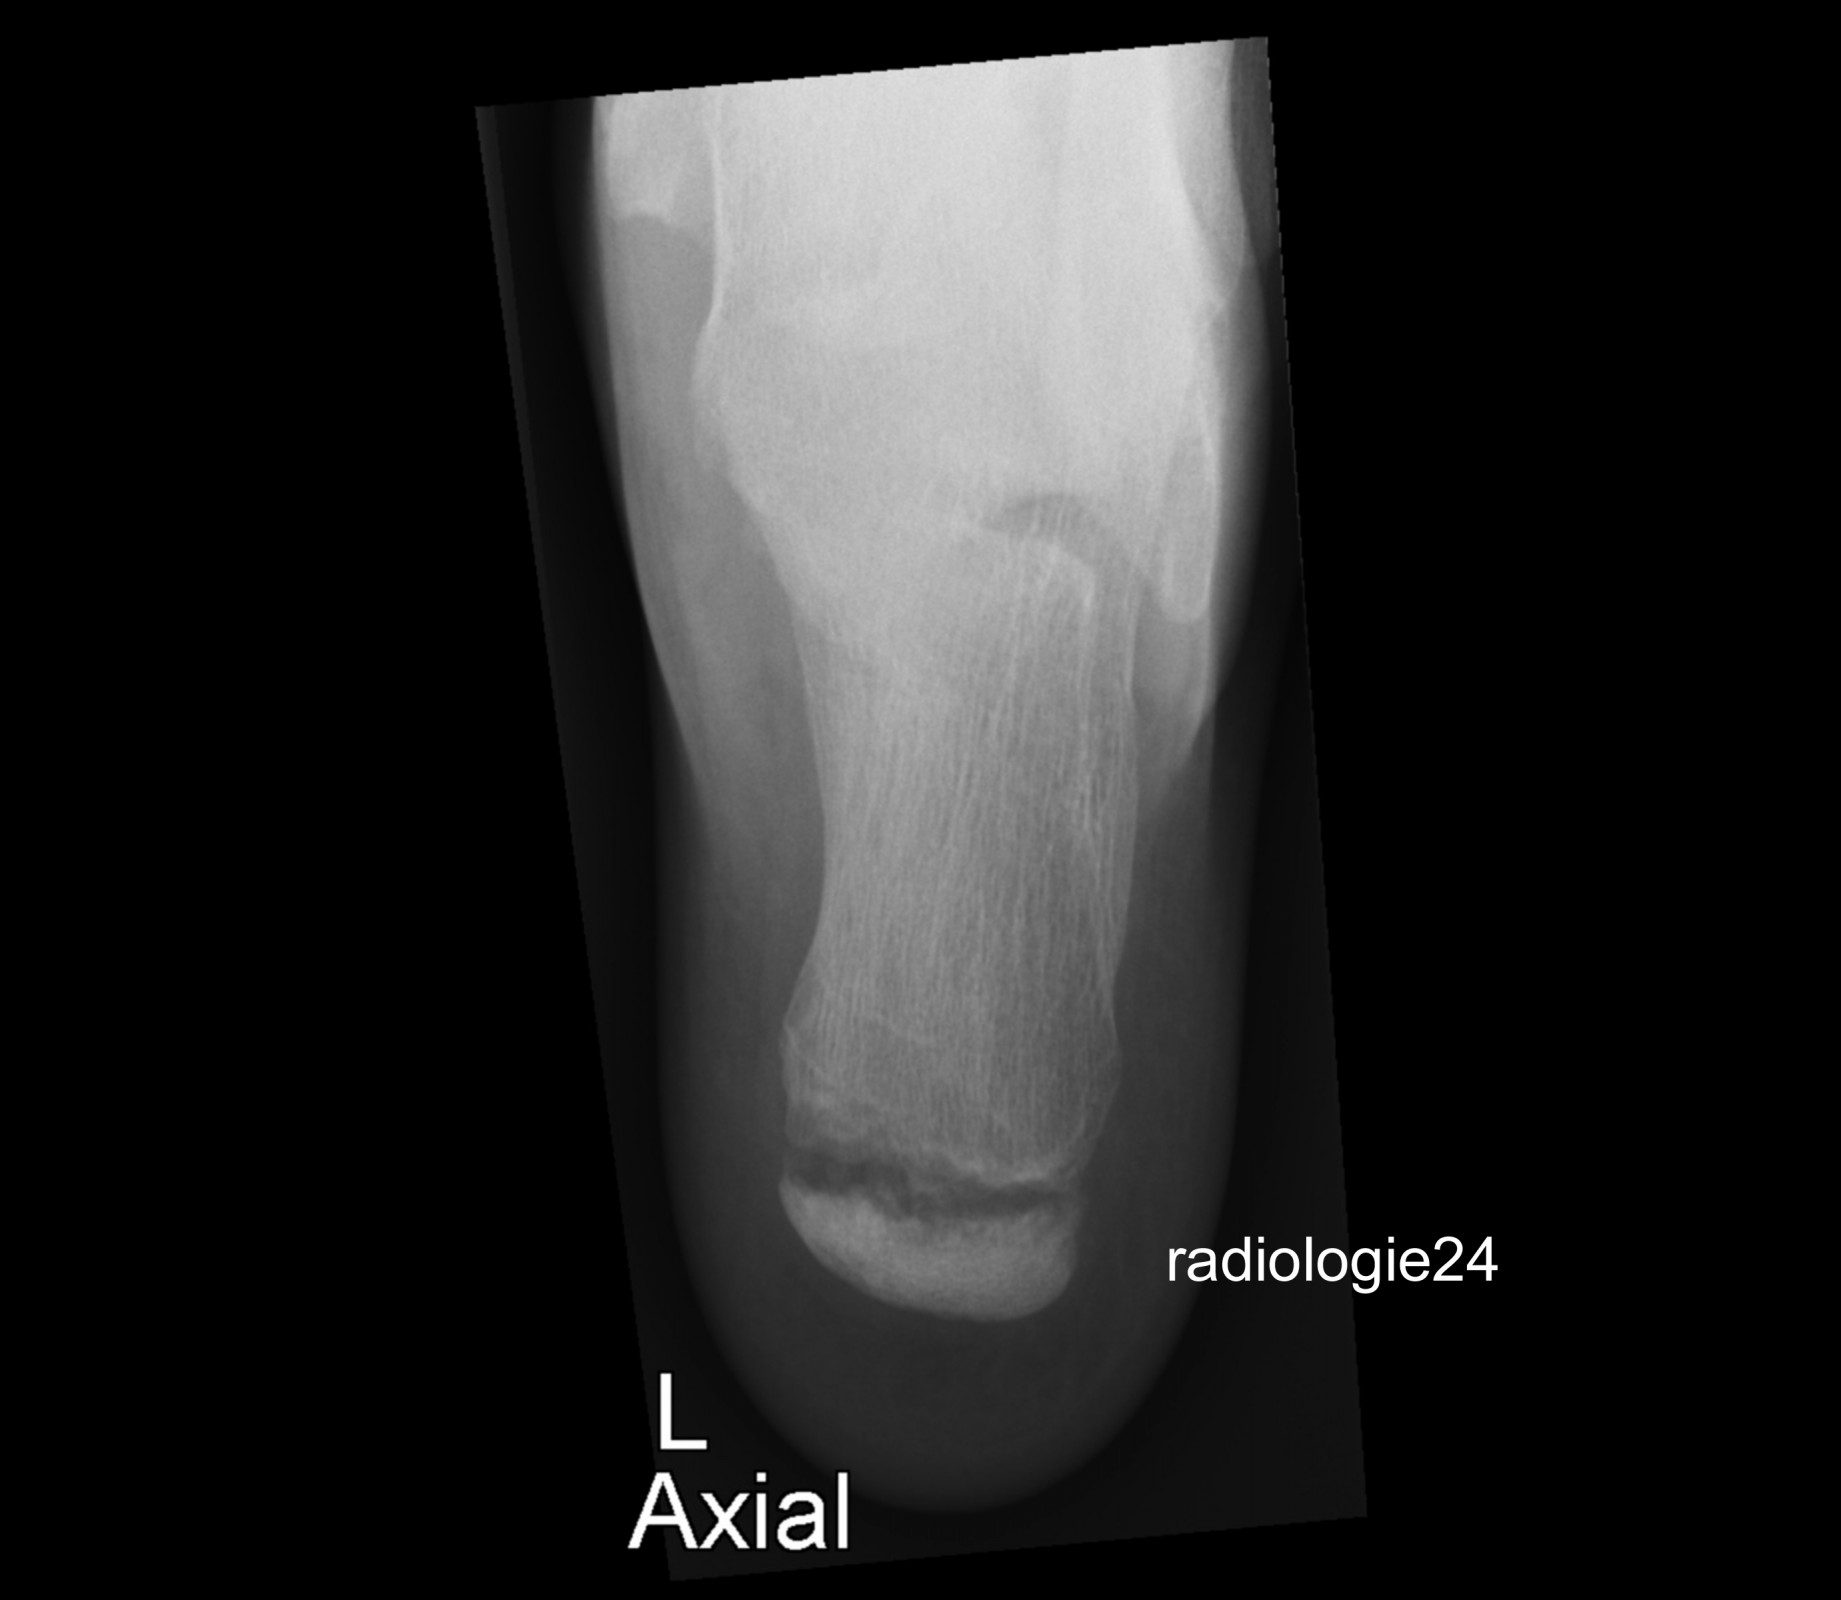

Röntgenfall des Monats April 2018 mit Auflösung

10 jähriger Patient Schmerzen im Bereich des Achillessehnenansatzes nach Fussballspiel. Ihre Diagnose? Weitere Abklärung?

Bild vergrössern